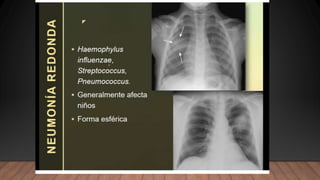

La neumonía causa un cuadro de condensación pulmonar producida por un exudado inflamatorio y proceso infeccioso que puede ser lobar, segmentario, intersticial, redondo o cavitario, siendo la forma lobar o alveolar la más común.